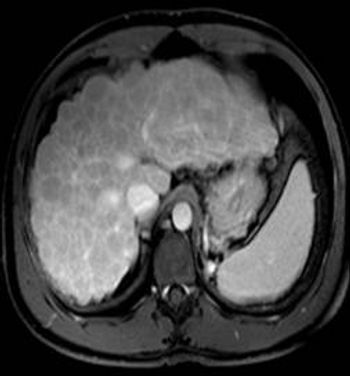

Image IQ: 67-year-old Male, Worsening Fatigue, JaundiceByDuke Duncan, MDFebruary 21st 201567-year-old male with history of worsening fatigue and jaundice.